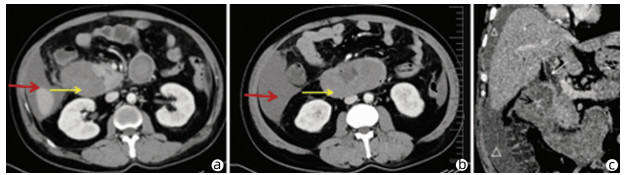

Heterotopic pancreas of the duodenum misdiagnosed as intraperitoneal tumor: A report of three cases

Abstract(697) HTML (326) PDF (3871KB)(37)

Abstract: